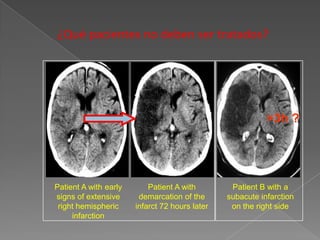

¿Qué pacientes no deben ser tratados?

>3h ?

Patient A with early       Patient A with        Patient B with a

signs of extensive      demarcation of the      subacute infarction

right hemispheric     infarct 72 hours later    on the right side

infarction